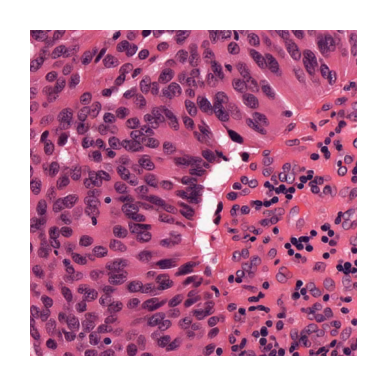

To see better what we are dealing with here, we show the image, first in its original form, and then with the desired centroids overlaid.

../../_images/7325a49b7276616c2d72a16cccc02c1d8d78a8483e59cf01b0c74bd47b64946c.png ../../_images/52d644e59037406b8566712af6a9d9810a6e4592b12593b534d104aad90ee62f.png